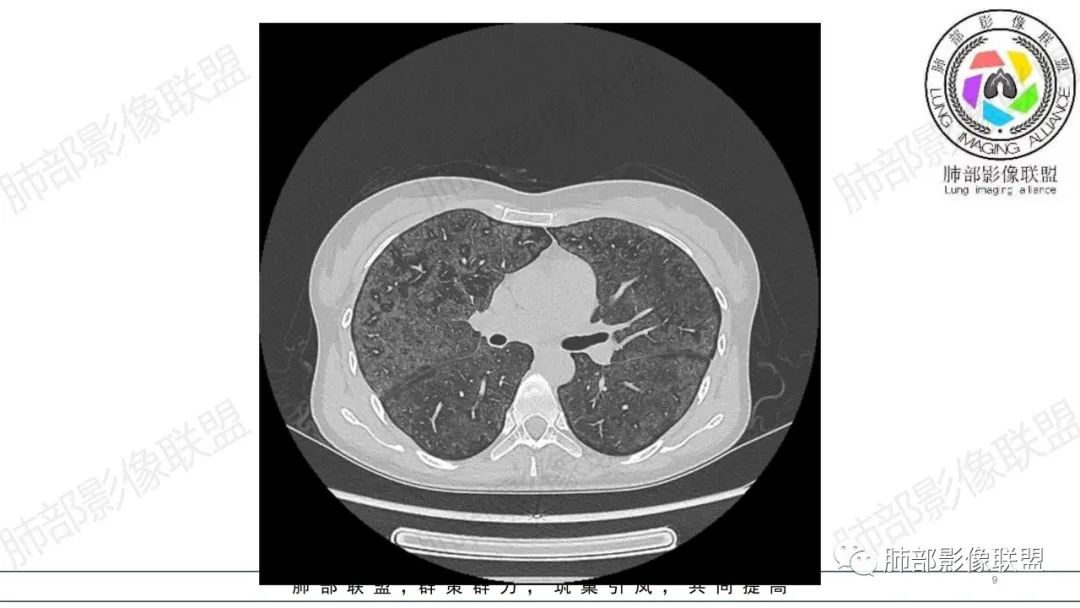

影像资料

34岁女性患者,“哮喘”病史30年,近期有可疑刺激性气体吸入史;因乏力半年,咳嗽、憋气、发热4天就诊;6.1CT提示双肺广泛毛玻璃影及粟粒样结节,胸膜下闲置及血管周闲置,可见树丫征,部分小叶间隔增厚。考虑:1.过敏性肺泡炎,有可疑刺激气体接触史,胸膜下闲置,广泛毛玻璃影,地图样分布,粟粒结节边界模糊,支持过敏性肺泡炎,但糖皮激素治疗效果不佳,且动态复查血常规血红蛋白进行性降低,过敏性肺泡炎 不符合;2.肺含铁血黄素沉积症:患者30“哮喘”病史,可能为肺含铁症状,肺部CT提示双肺弥漫毛玻璃影及粟粒结节影,中下肺明显,肺底部分小叶间隔增厚,近期咳嗽、憋气、发热,血常规血红蛋白进行性下降,考虑肺含铁急性期症状,但临床无咯血症状,肺含铁不典型。综合考虑:肺含铁血黄素沉积症>过敏性肺泡炎。

年轻女性 ,急性喘息发热,肺部影像弥漫磨玻璃密度,部分细小腺泡结节,胸膜下黑线显示,短期复查,病变密度增高,下肺明显,血管周围肺组织累及较少、且逐渐成小叶间隔分布。考虑弥漫肺泡内病变,并经淋巴道转移,下肺比上肺明显,多为免疫细胞功能下肺较强。1.过敏性肺泡炎,有相关病史,三层密度特点、头尾测分布,符合。2 肺泡微石症,多有钙化,且缓慢起病,病程不太符合,放待排。3 吸入相关肺损伤,有病史,疾病演变过程也符合渗出-肉芽肿改变,建议详细询问病史。4 感染性病变,结核?病变气道分布为主,如此弥漫且没有树丫不符合。5.巨细胞病毒,可以磨玻璃 结节 改变,没有免疫缺陷病史。最后考虑吸入所致 1过敏性肺泡炎、吸入性肺损伤 鉴别肺泡微石症。

肺内气腔磨玻璃结节,肝脾肿大,治疗后间质改变,弥漫大B可能